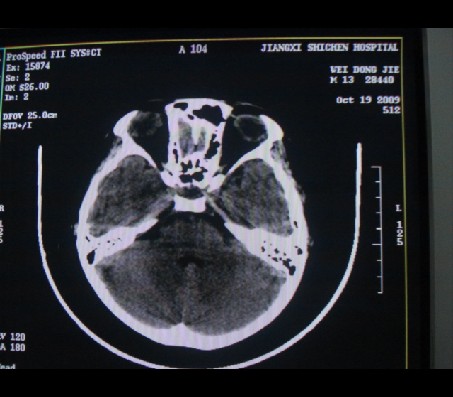

男性,12岁。反复头痛呕吐半月。脑积液无异常。病变部位ct值32hu,dwi无异常。

鞍内囊性占位性病变,t1wi、t2wi,均为高信号影。ct平扫为等密度。发病年龄较小。故首先考虑颅咽管瘤,可以做ct增强扫描

鞍内囊性占位性病变,t1wi、t2wi,均为高信号影。ct平扫为等密度。发病年龄较小。故首先考虑颅咽管瘤。